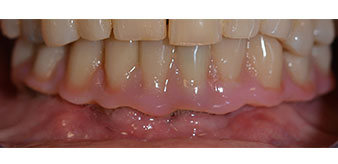

The 64-year-old patient presented with residual dentition of teeth 38, 33 and 43 and a clasp denture in the mandible (Fig. 1 and 2).

residual dentition

Fig. 1

Fig. 2